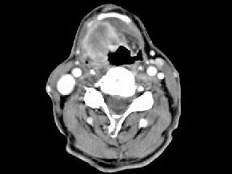

问题 男,63岁,咽喉部不适约一年,近2个月经常咳嗽,痰中带有血丝,CT如图所示,应诊断为 ( )

选项 A、声门上型喉癌 B、混合型喉癌 C、声门型喉癌 D、声门下型喉癌 E、梨状窝癌

答案 A